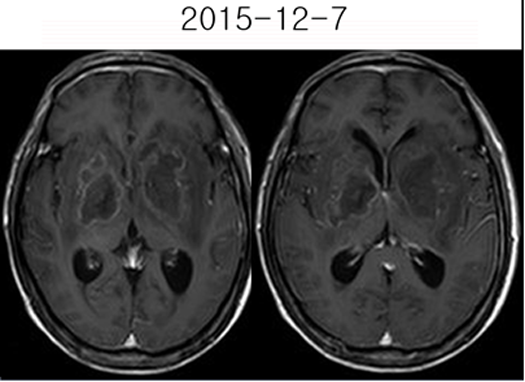

影像资料:

2015-11-27MR:双侧基底节区及双侧大脑脚示较对称片状异常信号, T1WI呈不匀低信号影,T2WI呈不匀高信号影,FLAIR序列呈不匀高信号,累及视交叉、视束及部分丘脑。2015-12-04复查:双侧基底节区及双侧大脑脚病灶范围较前稍增大。2015-12-07增强后病变呈多发环形薄壁或片状强化,DWI呈不均匀高信号。右侧基底节区病灶感兴趣区,可见Cho峰、NAA峰及Cr峰,Cho峰未见明显升高,Cho/Cr比值约为0.34,NAA/Cr比值约为0.56,Cho/NAA比值约0.61。综合平扫、增强、DWI、MRS所见,可排除肿瘤性病变,支持感染性病变(真菌或病毒感染可能性大)。